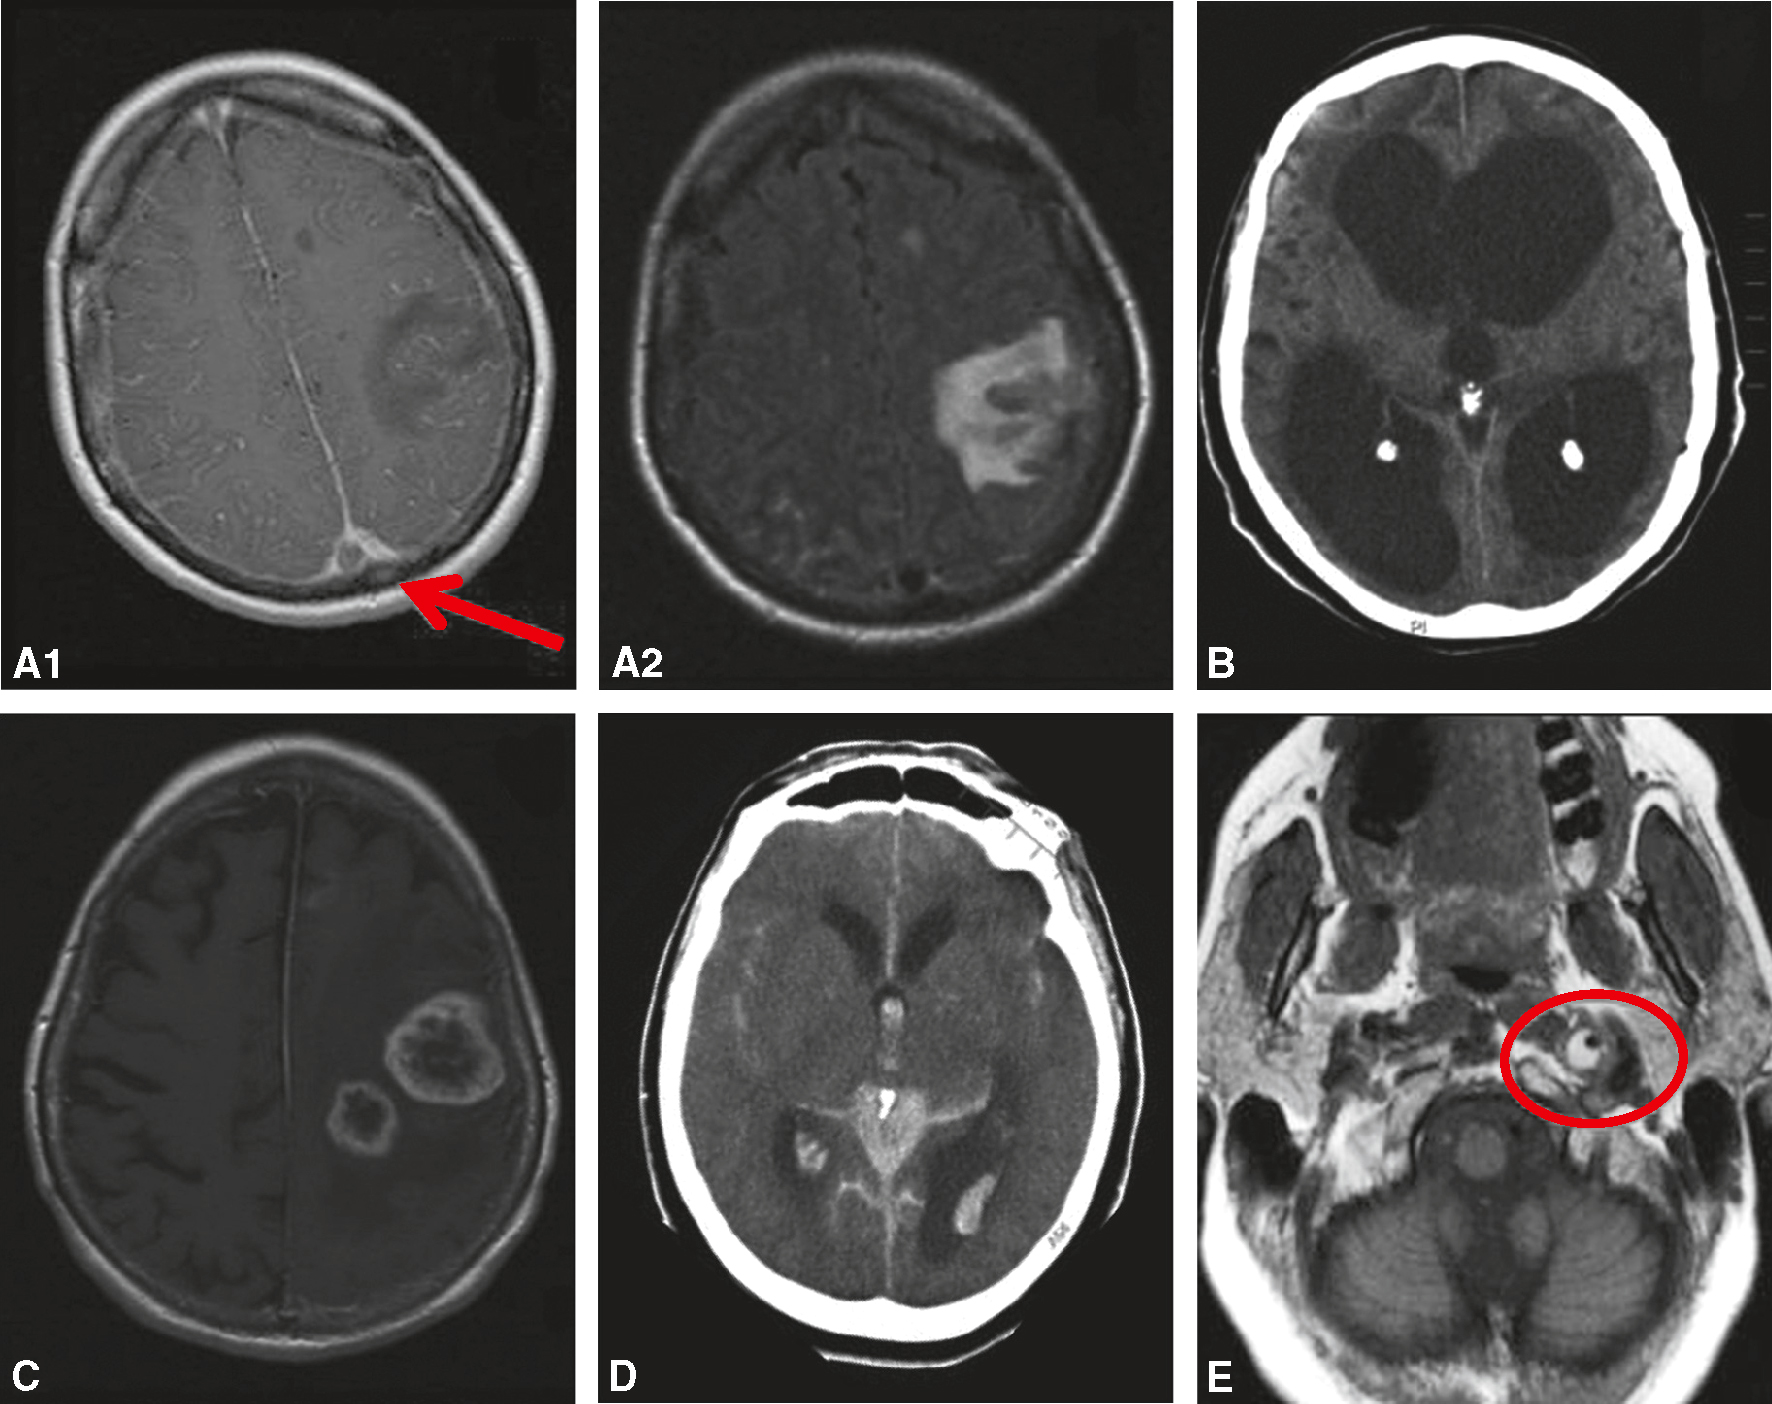

Fig. 11.2 Figure Exemples d’imagerie cérébrale de céphalées secondaires.

A. Thrombose veineuse cérébrale du sinus sagittal supérieur. IRM en séquence T1 avec gadolinium (A1 : thrombus responsable d’un signe du delta, flèche) et en FLAIR (A2 : infarctus veineux). B. Hydrocéphalie (scanner). C. Tumeur cérébrale (glioblastoma) (IRM). D. Hémorragie sous-arachnoïdienne (scanner). E. Dissection carotide interne gauche (IRM : hypersignal de la paroi artérielle en « croissant »).

L'image présente plusieurs exemples d'imagerie cérébrale de céphalées secondaires, c'est-à-dire des maux de tête causés par une condition médicale sous-jacente. Elle inclut six scans différents, chacun montrant des anomalies spécifiques dans le cerveau. A1 montre une IRM avec une flèche rouge pointant vers une lésion dans le lobe frontal droit. A2 présente une autre IRM avec une lésion similaire. B est une image de tomodensitométrie (CT scan) illustrant des zones de faible densité dans les hémisphères cérébraux. C est une autre IRM montrant une lésion dans le lobe pariétal droit. D montre une hémorragie intracérébrale sur une image de tomodensitométrie. Enfin, E est une IRM révélant une lésion dans la région du tronc cérébral, entourée par un cercle rouge. Ces images illustrent différentes causes de céphalées secondaires, telles que des tumeurs, des hémorragies et d'autres anomalies structurelles du cerveau. Elles sont essentielles pour diagnostiquer précisément les céphalées secondaires et déterminer les interventions médicales nécessaires.